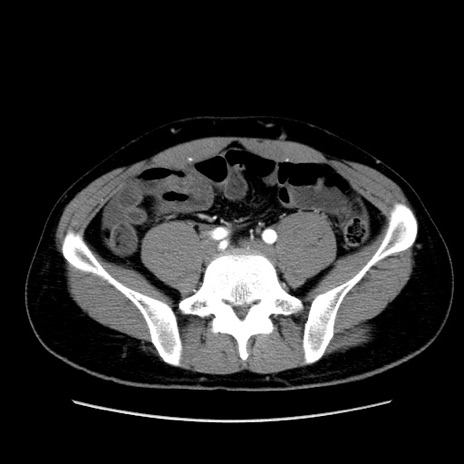

症例36(横断像)

【症例】20歳代 男性

【主訴】心窩部痛

【現病歴】今朝より上腹部痛あり。一旦軽快していたが再度出現したため救急要請。昨日夕に白身の魚を含む刺身を食べた。

【身体所見】BP 136/89mmHg、HR 74/min、BT 37.0℃、腹部:膨満、軟、心窩部に圧痛あり。反跳痛なし、筋性防御なし、腸雑音やや亢進あり。

【データ】WBC 17700、CRP 0.48